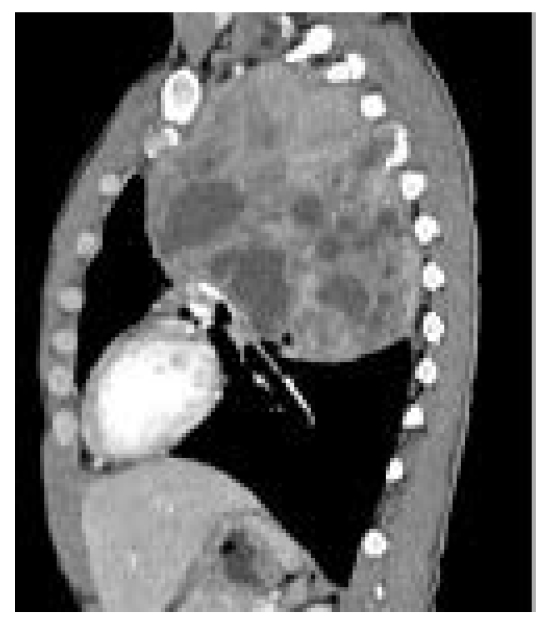

En el lóbulo inferior se notaron 6 pequeños nódulos de aspecto sólido. Así mismo, el hemitórax derecho evidenciaba 3 nódulos subpleurales menores de 6 mm, al igual que adenopatías de aspecto atípico en el nivel ganglionar intravenoso izquierdo del cuello y en el mediastino (figura 5).

Figura 5. Tomografía contrastada, reconstrucción sagital

Para completar el abordaje, se le realizó al paciente una gammagrafía ósea que evidenció un tumor dependiente de vértebras torácicas que infiltraba el pulmón izquierdo y se introducía en el foramen vertebral de D3-D4, D4-D5, además de metástasis en los arcos costales cuarto y quinto izquierdos (figura 10).

Figura 10. Gammagrafía ósea vértebras D3-D4, D4-D5 con infiltración en pulmón izquierdo y arcos costales 4to y 5to izquierdos.